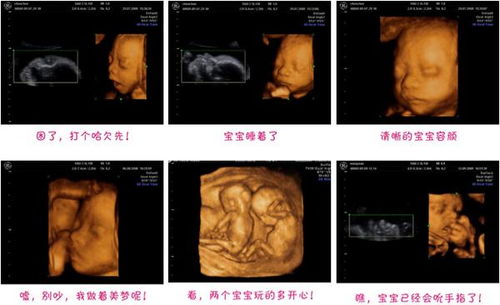

随着孕期进入30周,准妈妈们即将迎来一个重要的检查时刻——孕30周系统彩超。这一检查对于监测胎儿健康状况、评估孕期风险具有重要意义。本文将为您详细介绍孕30周系统彩超的相关知识,帮助准妈妈们更好地了解这一检查的重要性。

孕30周系统彩超是孕期中非常重要的一项检查,其主要目的是全面了解胎儿的生长发育情况、羊水量、胎盘功能、脐带血流情况等,从而评估胎儿的健康状况。此外,系统彩超还能帮助医生及时发现胎儿畸形、发育异常等问题,为孕期保健提供有力支持。